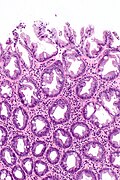

Hyperplastic polyp. H&E stain. | |

Microscopic

Features:[1]

- Irregular crypt architecture - tortuosity.

- Serrated epithelial cells (at the surface of the gland) - only colorectal polyps - key feature.

- Serrated appearance = saw-tooth appearance, epithelium has jagged edge.

Notes:

- Significant negatives:

- No nuclear atypia; glands darker staining deep... lighter staining luminal.

- In the colon goblet cells should be present (as is usual).